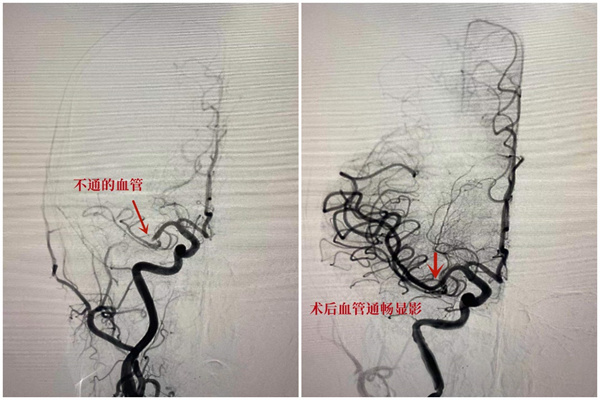

18分钟让大脑血流再次通畅

伍建明主任团队立即为患者进行“全脑血管造影及机械取栓术”,在医生娴熟的操作下,将直径不到1mm的微导管,在微导丝的导引下穿过左侧中动脉栓塞部位,微导管造影血管远端通畅,用中间导管1次抽吸,就将堵塞血管的罪魁祸首“血栓”精准捕获并拉出体外。仅18分钟,血管已经恢复再通,血流速度正常。目前患者生命体征平稳,意识和肢体功能正在逐步恢复中。(记者 林丽青)